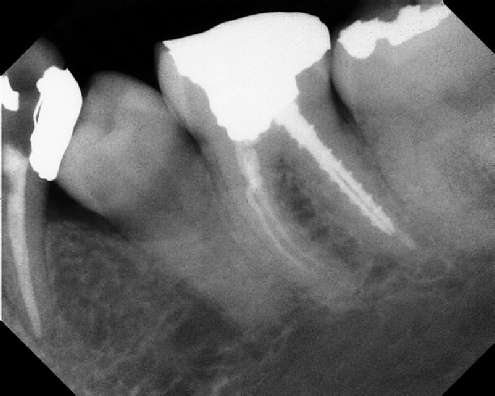

Root Canal Retreatment - Meriden 8 mos. recall Post-op Pre-op